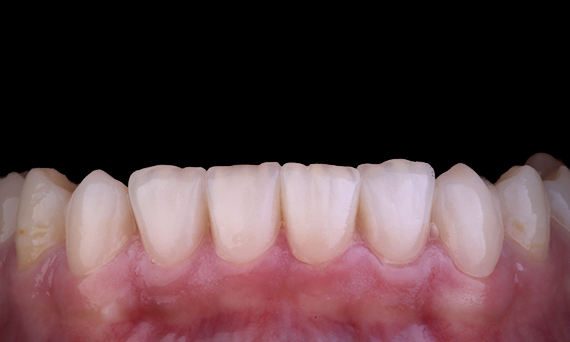

El paciente presentó periodontitis apical asintomática en la pieza dental 34. A partir de la radiografía preoperatoria, se observó que la pieza dental 34 tenía dos raíces visibles. Sin embargo, un escaneo CBCT confirmó un premolar de tres raíces y los canales se dividieron en tres en la raíz media. Una cuidadosa selección de limas es fundamental para este diente delicado.

Dr. Jack Lin, endodoncista, Sídney, NSW Australia

En esta situación, la preservación de la estructura del diente/raíz es esencial para reducir el riesgo de reborde, transporte, cierre, perforación y fractura de la raíz. La selección de casos, el diagnóstico y la planificación previa al tratamiento son importantes. La selección de limas de endodoncia con flexibilidad, eficiencia y respeto por la anatomía de la raíz natural es fundamental.